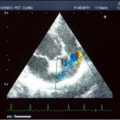

C:超音波画像 肺動脈領域の異常血流

左側胸壁よりLevine 4/6の連続性心雑音が聴取された。胸部レントゲン検査において心拡大が認められ、超音波検査においても肺動脈領域に連続的な異常血流が観察された。大学病院を紹介受診され、手術が行われた。現在はACE阻害薬のみの内服で補助的治療を行っている。